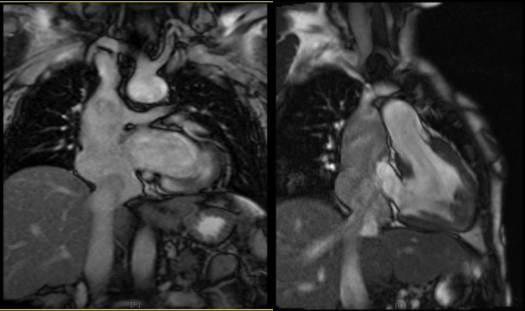

A 30 years old Male with history of complex congenital disease as  Abdominal and atrial situs solitus, , Levocardia , L-looped ventricles, Dominant left sided ventricle with RV morphology with moderate to severe systolic dysfunction(GEF:35%), also Both AV-valves empty to RV(DIRV),Moderate to severe left and right AV valve regurgitation, Both great arteries arise from dominant ventricle(DORV),Aorta was anterior and right sided to PA(D-malposition of great arteries),PA closed surgically with no ante grade flow,  confluent PA branches(RPA=1.4mm,LPA=1.4mm),Left sided aortic arch, Patent Glenn shunt with normal respiratory variation and low velocity laminar flow,Patent conduit between IVC and RPA with slow flow ,4mm fenestration with MPG:4 mmHg, Moderate size secondum type ASD( Fontan surgery, intracardiac tunnel with fenestration).(fig1,2,3)

Fig. 1: Echocardiography in standard apical 4 chamber showed  Both AV-valves empty to RV

Figure 1